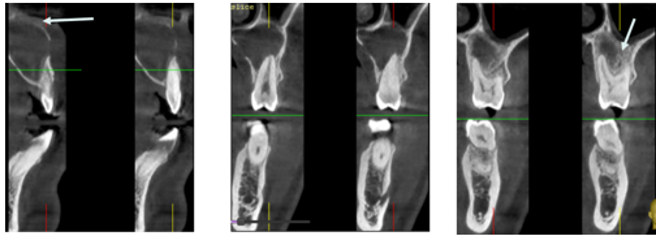

Regarding the large extension of the lesion associated to cortical rupture of the sinus and nasal floor, a staged surgical approach was undertaken, involving cyst decompression with drain placement (Figure 3). A biopsy of the cystic lesion was obtained and sent for histopathological examination. Microscopically, the specimen revealed a cystic cavity lined by stratified squamous keratinized epithelium with a dense connective tissue wall. At low magnification, the cystic lumen was observed to be lined by parakeratinized stratified squamous epithelium. The epithelial lining consisted of five to seven cell layers, consistent with the characteristic thickness of OKCs. Palisading of the basal cells was noted, further supporting the diagnosis. These histopathological features confirmed the final diagnosis of parakeratinized OKC.

Figure 3 Intraoperative image showing decompression with drain placement.

A radiological follow-up after four months revealed the onset of bone trabeculation at the cystic periphery, along with the formation of a thin bony capsule at the nasal and sinus floor (Figure 4), which was the primary decompression goal.

Figure 4 CBCT 4 months after decompression showing formation of a thin bony layer at the nasal and sinus floor.